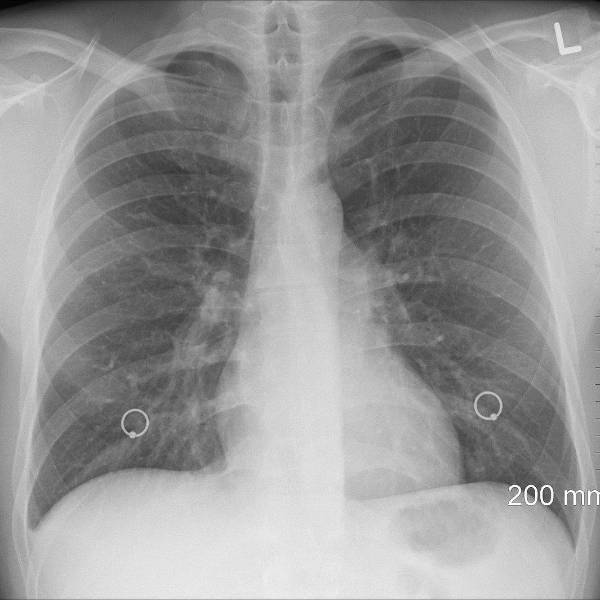

La bacteria no se transmite de persona a persona, sino que lo hace por vía inhalatoria o a través del agua. Provoca fiebre e infección pulmonar

Afirmó que la bacteria no se transmite de persona a persona, sino que lo hace por vía inhalatoria o a través del agua. Provoca fiebre e infección pulmonar y fue identificada tras estudios del Instituto Malbrán, referente nacional en infectología.

Los ocho nuevos pacientes fueron incorporados al registro al ampliar el criterio de inclusión, a partir de que se conoció que la bacteria causante no siempre produce neumonía bilateral. Se contabilizan 19 contagios hasta la fecha.

La semana pasada una serie de decesos por una neumonía bilateral agresiva habían alertado a las autoridades sanitarias, que tras primeros análisis descartaron que se tratara de covid-19, gripe, influenza o hantavirus.